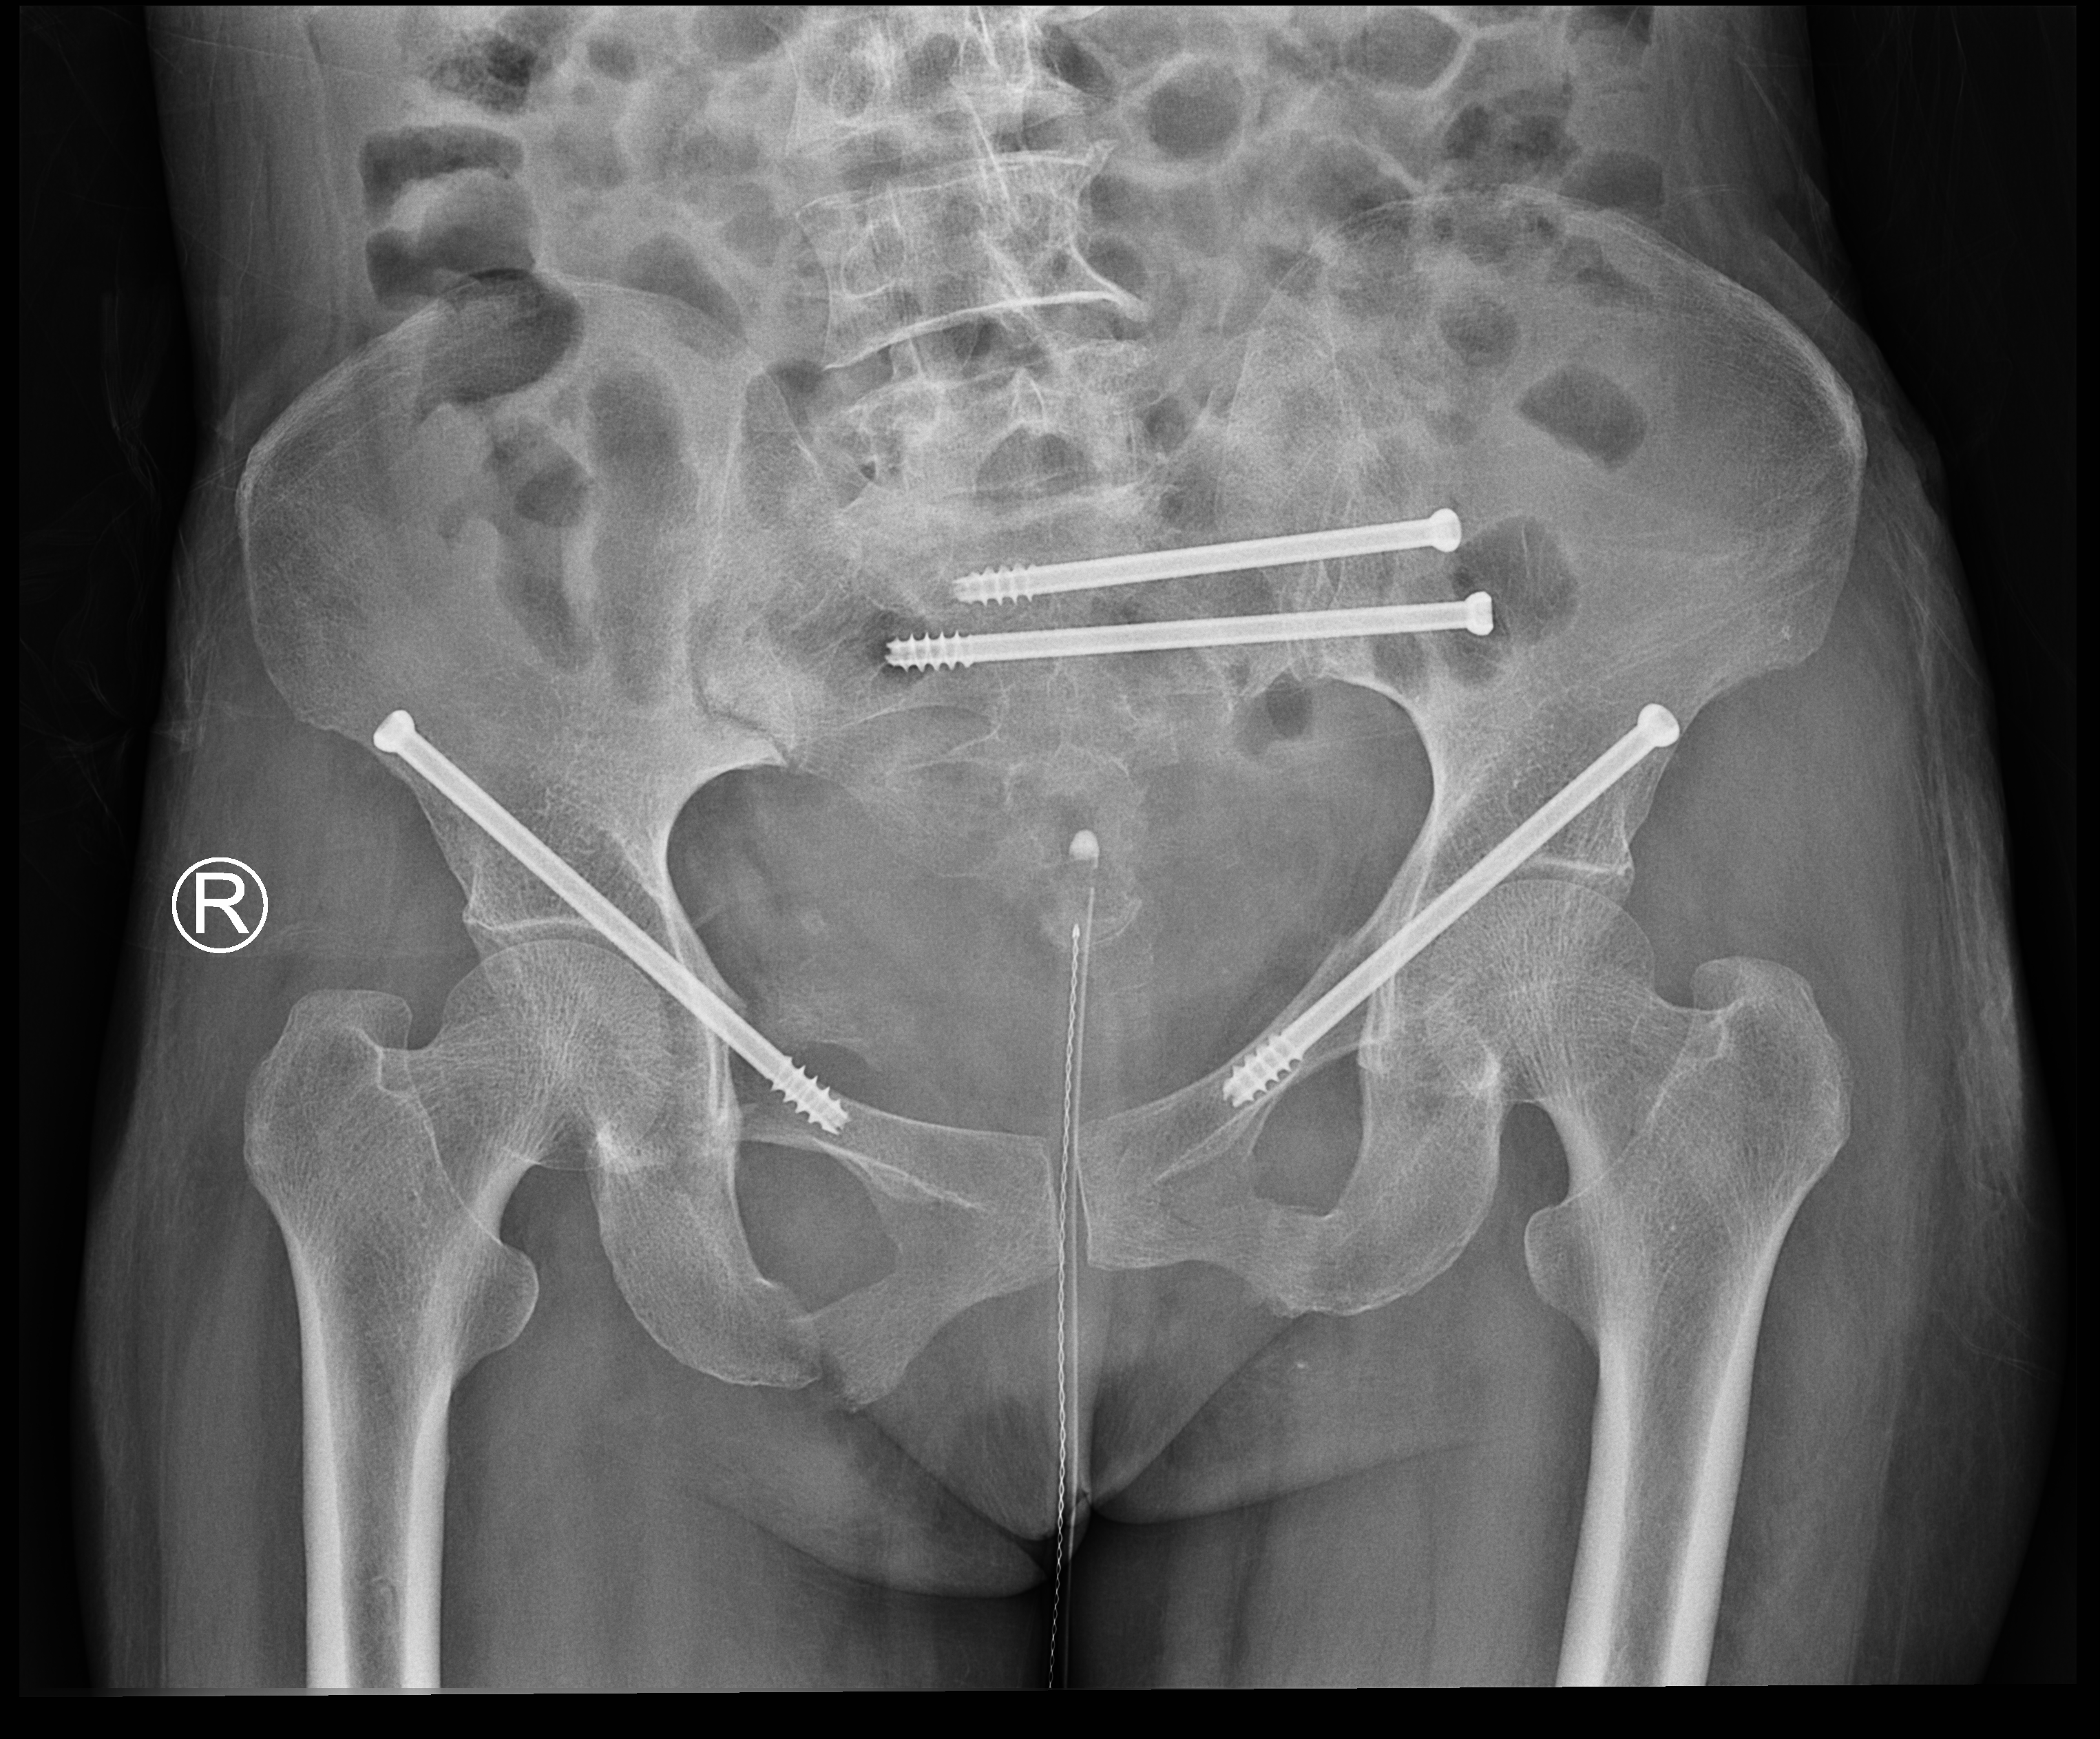

术后